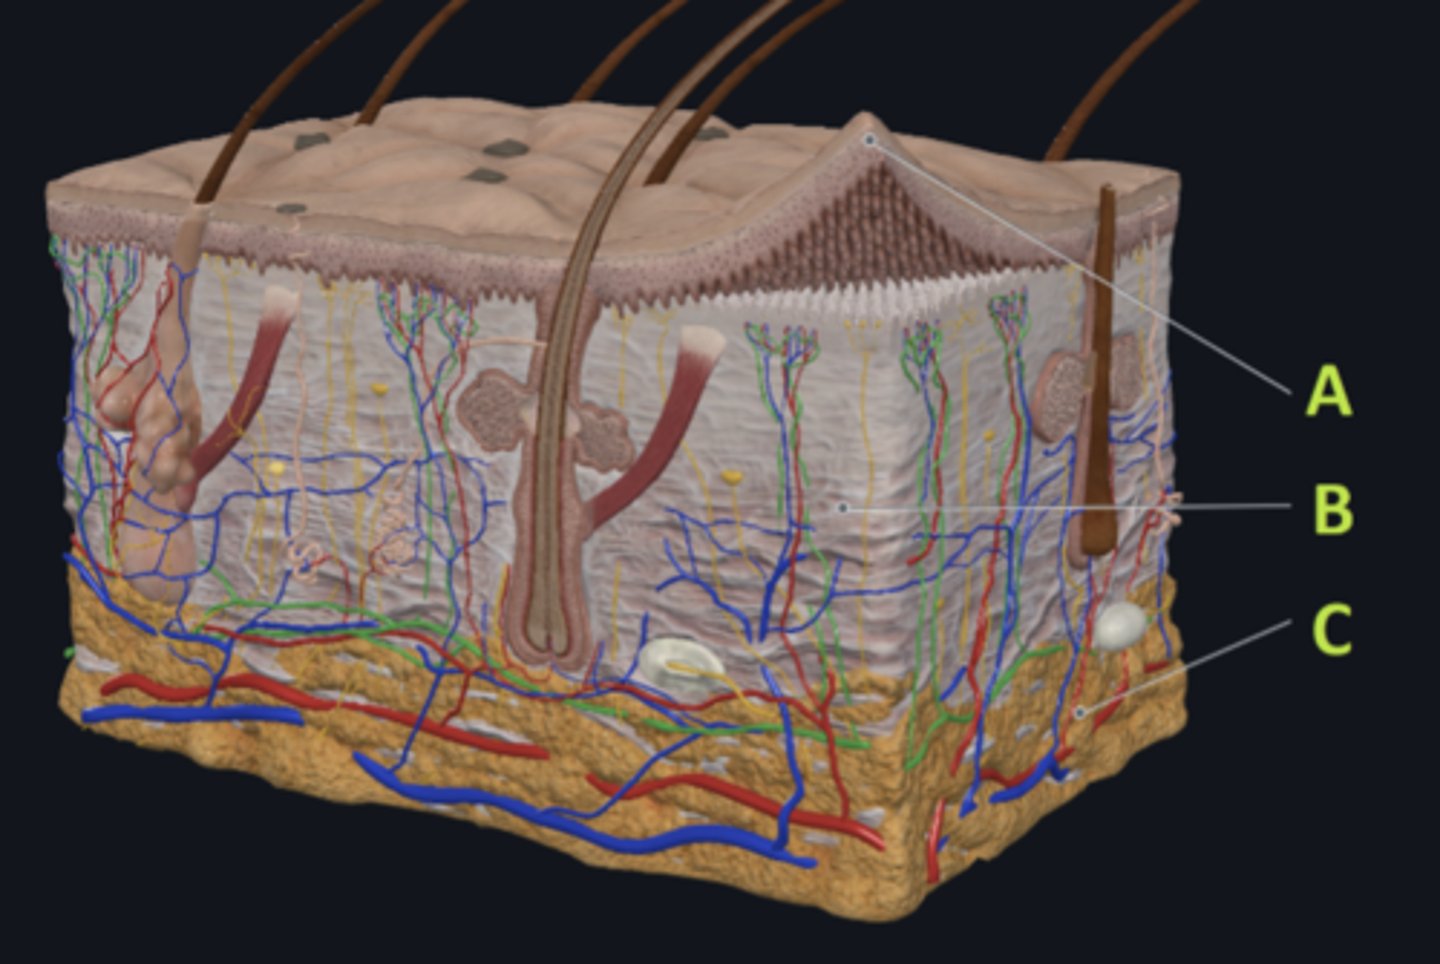

C - hypodermis

Answer the following questions based on the features indicated in the following image. Which letter indicates the administration site for subcutaneous injections?

A - epidermis

Answer the following questions based on the features indicated in the following image. Which letter indicates the administration site for topical creams and ointments?

B - Dermis

Answer the following questions based on the features indicated in the following image. Which letter indicates the administration site for the tuberculin skin test?

A - epidermis

Answer the following questions based on the features indicated in the following image. Which letter indicates a region of the skin with no nerves or blood vessels?

B - Dermis

Answer the following questions based on the features indicated in the following image. Which letter indicates the region where skin appendages (sweat glands, sebaceous glands, and hair follicles) have their roots?

Epithelial tissue

Answer the following questions based on the features indicated in the following image. Which of the four major tissue types is indicated by letter A?

Which letter indicates the administration site for insulin injections?

A

Which letter indicates the administration site for a lidocaine patch?

B

Which letter indicates the administration site for an allergy test?

B

Which letter indicates a region of the skin rich in dense, irregular connective tissue?

C

Which letter indicates the region most important for energy storage and thermal insulation?

Connective

Which of the four major tissue types is indicated by letter C?